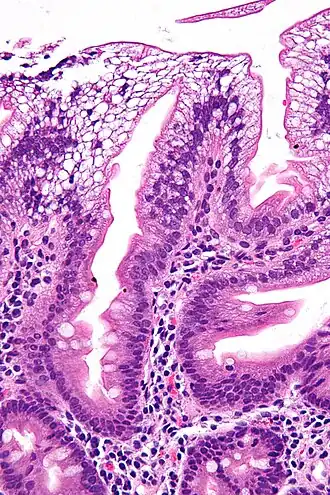

![]() Micrografía de una biopsia duodenal que muestra enterocitos con un citoplasma claro (debido a la acumulación de lípidos) característico de la abetalipoproteinemia. | ||

La abetalipoproteinemia o síndrome de Bassen-Kornzweig, es una rara enfermedad, autosómica recesiva, que afecta al tracto digestivo, cuya principal característica es la incapacidad que tiene el organismo de absorber adecuadamente los componentes grasos del alimento a través del intestino, lo que tiene como consecuencia la producción de heces grasosas (esteatorrea), deficiencia en el desarrollo infantil y problemas en los nervios.[1] La enfermedad se caracteriza por niveles bajos o ausentes de colesterol plasmático, lipoproteínas de baja densidad y lipoproteínas de muy baja densidad. No debe confundirse con una deficiencia de beta-lipoproteínas. Los síntomas característicos incluyen malabsorción de grasas, degeneración espinocerebelosa, acantocitosis y retinosis pigmentaria.[2]